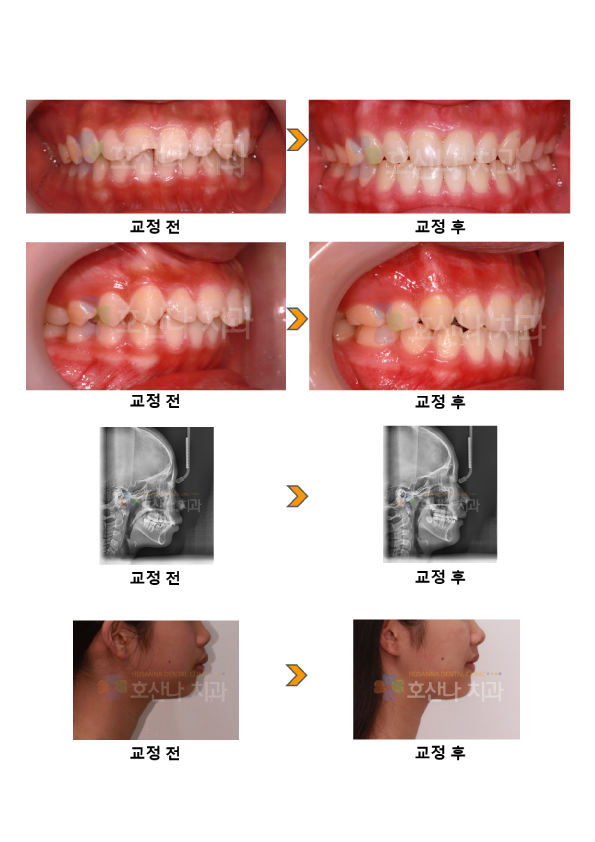

< 비수술 돌출입교정 시술증례 >

1. 치료대상

10대 female

2. 환자분 c.c

① 치아가 잘 안맞물려요.

② 입이 나왔어요.

3. Dr.Koo Memo

돌출과 크라우딩으로 내원하신 예쁜 10대 소녀입니다.

안타깝게도 앞니는 외상으로 인해 깨져있었습니다.

상,하악 전치가 뻐드러져 있고 특히 상악전치가 많이 앞으로 나와 있는 경우 정상인 경우 보다 앞니가 부딪히는 외상에 노출 되기 쉽습니다.

돌출을 해소하기 위해 발치교정을 택하였고 다친 #11번의 치아는 이후 관찰 하였습니다.

교정 후 돌출이 해소되어 입술라인이 자연스러우며 스마일도 좋아졌네요 .

아직 어려서 파절된 #11은 레진으로 수복해주었습니다.

4. 교정기간

2y 3m